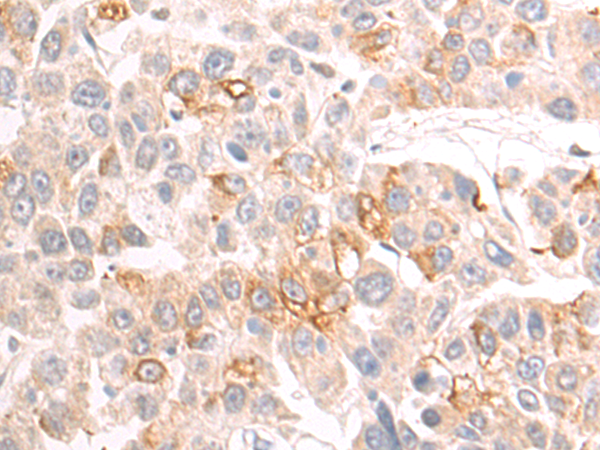

分类: 科研抗体货号: P03693别名: MPFYVE应用: WB,IHC反应种属: Human